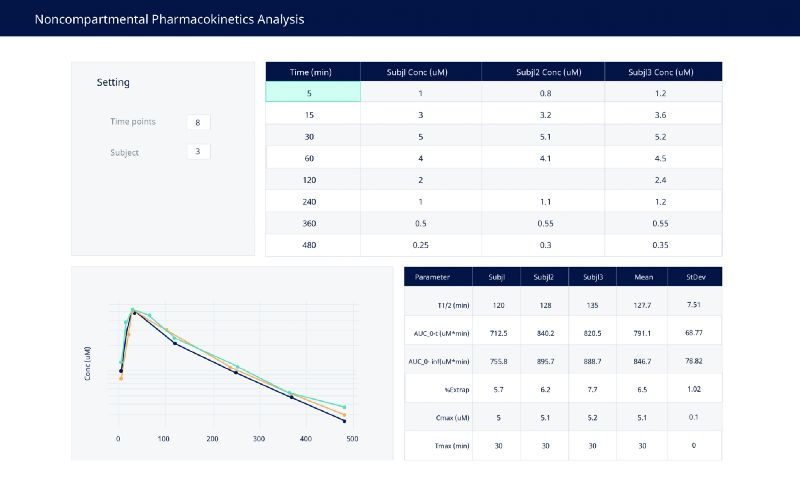

3. 进行药代动力学分析

此 Dash 应用程序旨在允许进行药代动力学研究的人员输入数据(手动或通过复制粘贴)。然后显示浓度 - 时间曲线以及用 Python 计算的各种参数表。

使用自定义的Dash应用程序简化了pk分析